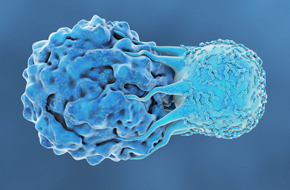

Explore how the novel HuGEMM™ and HuCELL™ platforms can assess the efficacy of your molecule and accelerate your immuno-oncology drug discovery programs.